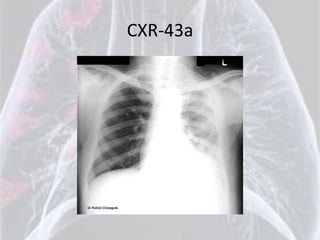

CXR-43a

CXR-43b

Diagnosis is: Mesothelioma

Mesothelioma

•   Unilateral haziness

•   Smaller left hemithorax

•   Chest wall swelling

•   Loss of diaphragmatic silhouette

•   Blunting of costophrenic angle

•   Pleural thickening / Mass